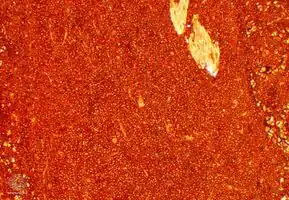

Association with the Epstein–Barr virus

Rarely, the Epstein–Barr virus (EBV) is associated with multiple myeloma and plasmacytomas, particularly in individuals who have an immunodeficiency due to e.g. HIV/AIDS, organ transplantation, or a chronic inflammatory condition such as rheumatoid arthritis.[11] EBV-positive multiple myeloma and plasmacytoma are classified together by the World Health Organization (2016) as Epstein–Barr virus-associated lymphoproliferative diseases and termed Epstein–Barr virus-associated plasma cell myeloma. EBV-positivity is more common in plasmacytoma than multiple myeloma. The tissues involved in EBV+ plasmacytoma typically show foci of EBV+ cells with the appearance of rapidly proliferating immature or poorly differentiated plasma cells.[12] These cells express products of EBV genes such as EBER1 and EBER2. EBV-positive plasmacytoma(s) is more likely to progress to multiple myeloma than EBV-negative plasmacytoma(s) suggesting that the virus may play a role in the progression of plasmacytoma to multiple myeloma.[13]